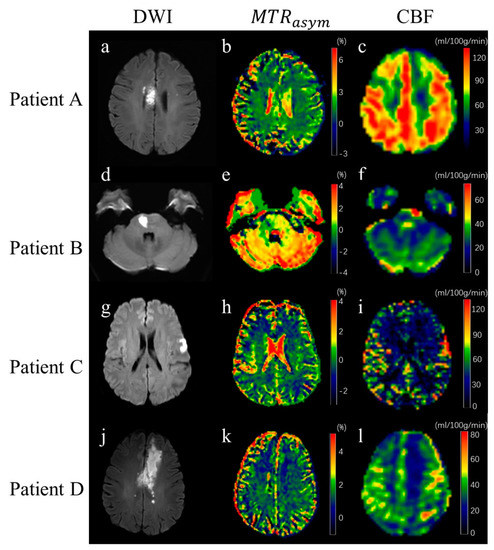

3.2. Image of Stroke Patients